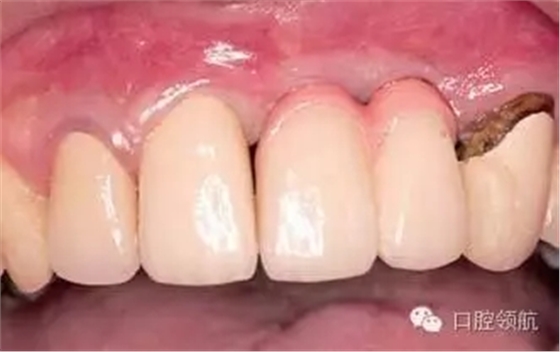

可以選擇在(右上第1、2顆牙) 部位的唇側(cè)進(jìn)行結(jié)締組織移植來(lái)獲得牙齦組織美學(xué)形態(tài)連續(xù)性的恢復(fù)的外科方式。在本病例中,因?yàn)榛颊卟皇锹洱l笑的類(lèi)型,所以選擇了用修復(fù)的辦法提高美學(xué)效果,在金屬基底冠上,使用牙齦瓷,來(lái)恢復(fù)牙齦形態(tài)對(duì)稱性(圖2、圖3)。

圖2 戴入上部基臺(tái)的狀態(tài)。

圖3 戴入有牙齦瓷的金屬基底烤瓷冠,(右上第3顆牙) 是不良修復(fù)體,計(jì)劃在(右上第1、2顆牙)種植區(qū)周?chē)能浗M織穩(wěn)定后,再對(duì)(右上第3顆牙) 進(jìn)行重新修復(fù)。